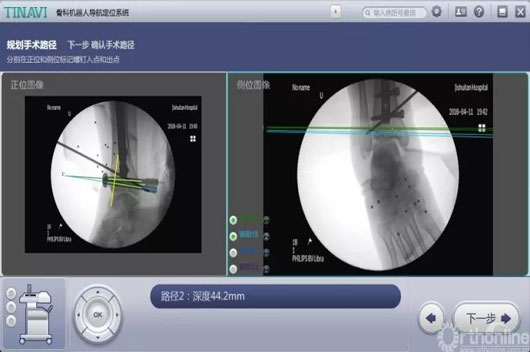

3.jpg

术中妄想后踝螺钉位置